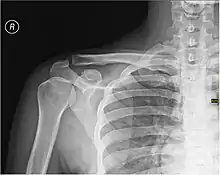

Каркасом плеча служит плечевая кость.

При травмах плеча возможно повреждение нервов и сосудов, а также переломы плечевой кости, наиболее частой локализацией которых является шейка плечевой кости.[1]